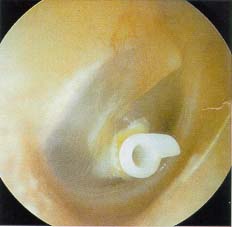

»ïÃ⼺ ÁßÀÌ¿° °í¸·»çÁø

Æ©ºê »ðÀÔ °í¸·»çÁø